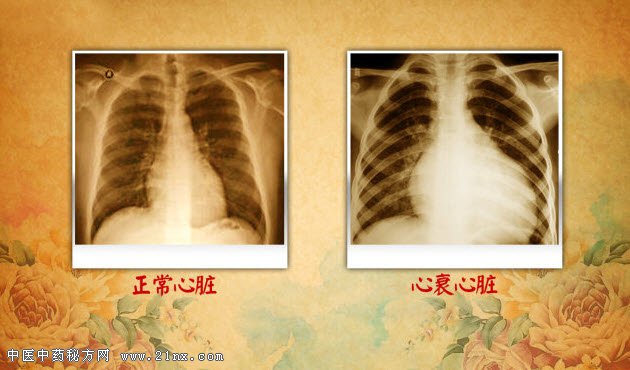

图:正常心脏和心衰心脏 身体里那只危险的“蝴蝶”,位于气管的前方。如果是比较瘦的观众,可以尝试自己摸一下。手指放在气管中下部,咽口口水,质地较韧的就是。它是人体最大的内分泌腺体,它是人体代谢和发育的主要调控者。它们能够增加人体的代谢、促进生长发育、提高神经系统和心血管的兴奋性等。因为心脏是这种激素重要的作用靶器官,并通过直接或间接的作用影响心率和心肌收缩力。要说它与心脏病的关系,可以说非常“暧昧”。打个比方,它是心血管系统的“司令部”,它下达命令,心脏就要执行。它到底是什么器官?扫描并关注养生堂微信公众号,答案在等着您。 老年人和女性是这种疾病的高发人群。一半以上的患者不知晓自己的病情,或者症状很轻,常误认为抑郁或更年期的症状。没有及时治疗,后果可以很严重。中华医学会内分泌分会于2010 年公布的“中国十城市社区居民疾病流行病学调查”结果,在被调查的15181 例中国城市人群中,它的患病率是6.5%。到底它是哪个器官,会对心脏造成什么影响呢?敬请关注本期《养生堂》为您带来的《揭开迷雾保心脏》。